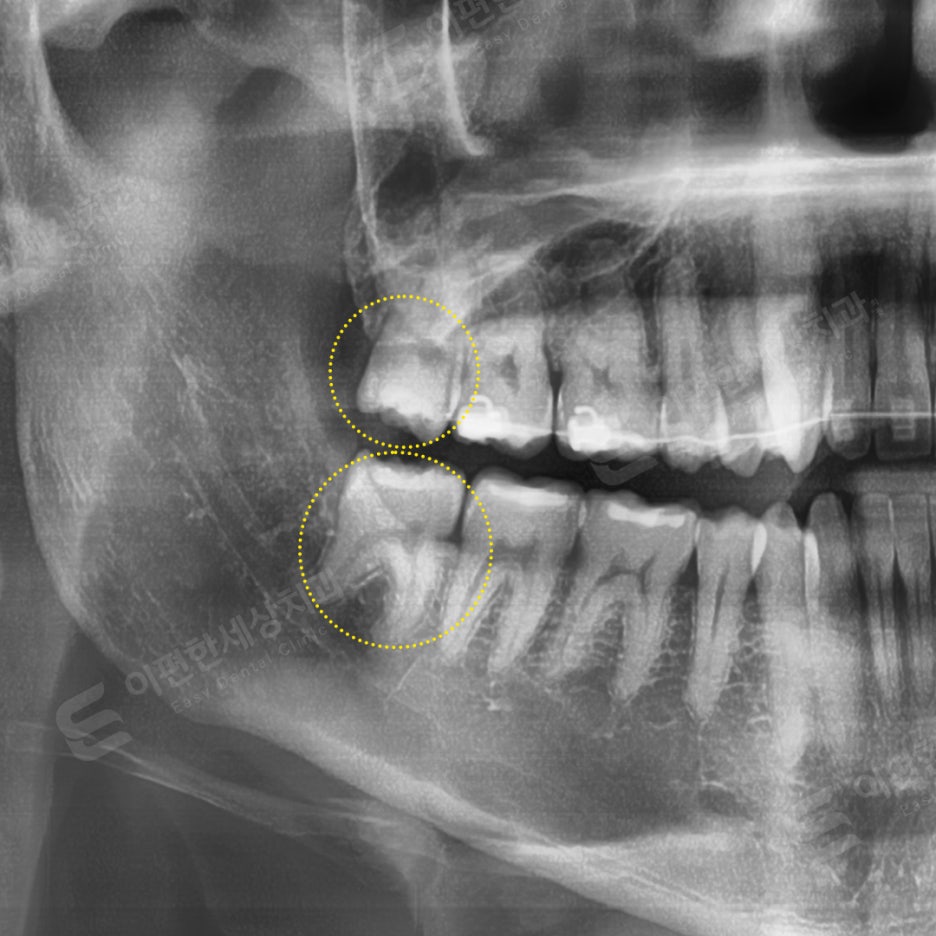

촬영 일자 24. 03. 11

사랑니 검진 후 당일 발치 케이스

#48 완전매복 발치

bur로 골 삭제 후 치아 분할하여 발치,

치근과 하악관 겹쳐보여 CT 촬영 후 발치

#18 일반 발치